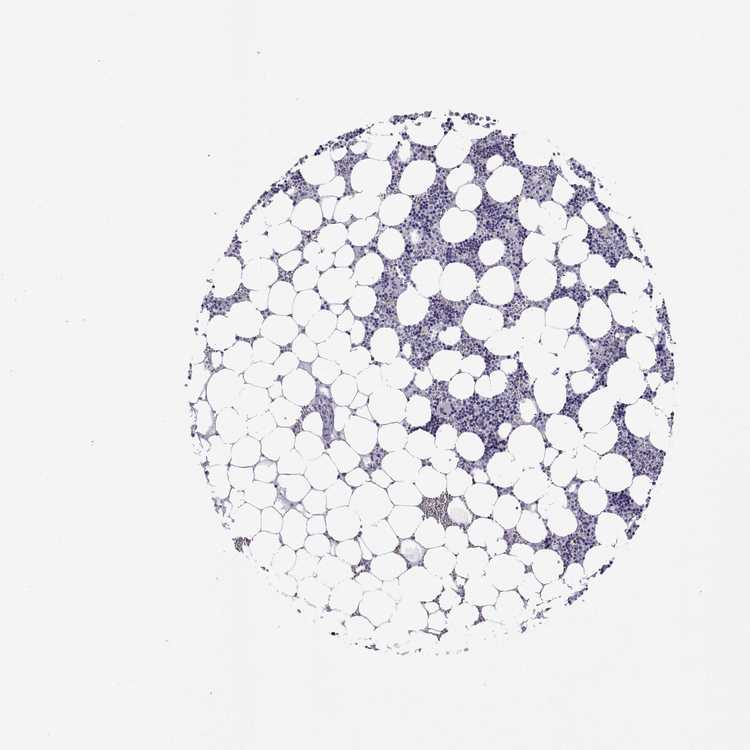

TISSUE PRIMARY DATA BONE MARROW Show tissue menu

Bone marrow

BONE MARROW - Antibody stainingi

Antibody staining in the annotated cell types in the current human tissue is reported as not detected, low, medium, or high, based on conventional immunohistochemistry profiling in selected tissues. This score is based on the combination of the staining intensity and fraction of stained cells.

Each image is clickable and will lead to virtual microscopy that enables deeper exploration of all samples and also displays staining intensity scores, fraction scores and subcellular localization as well as patient and tissue information for each sample.

Antibody HPA055583

Hematopoietic cells Not detected